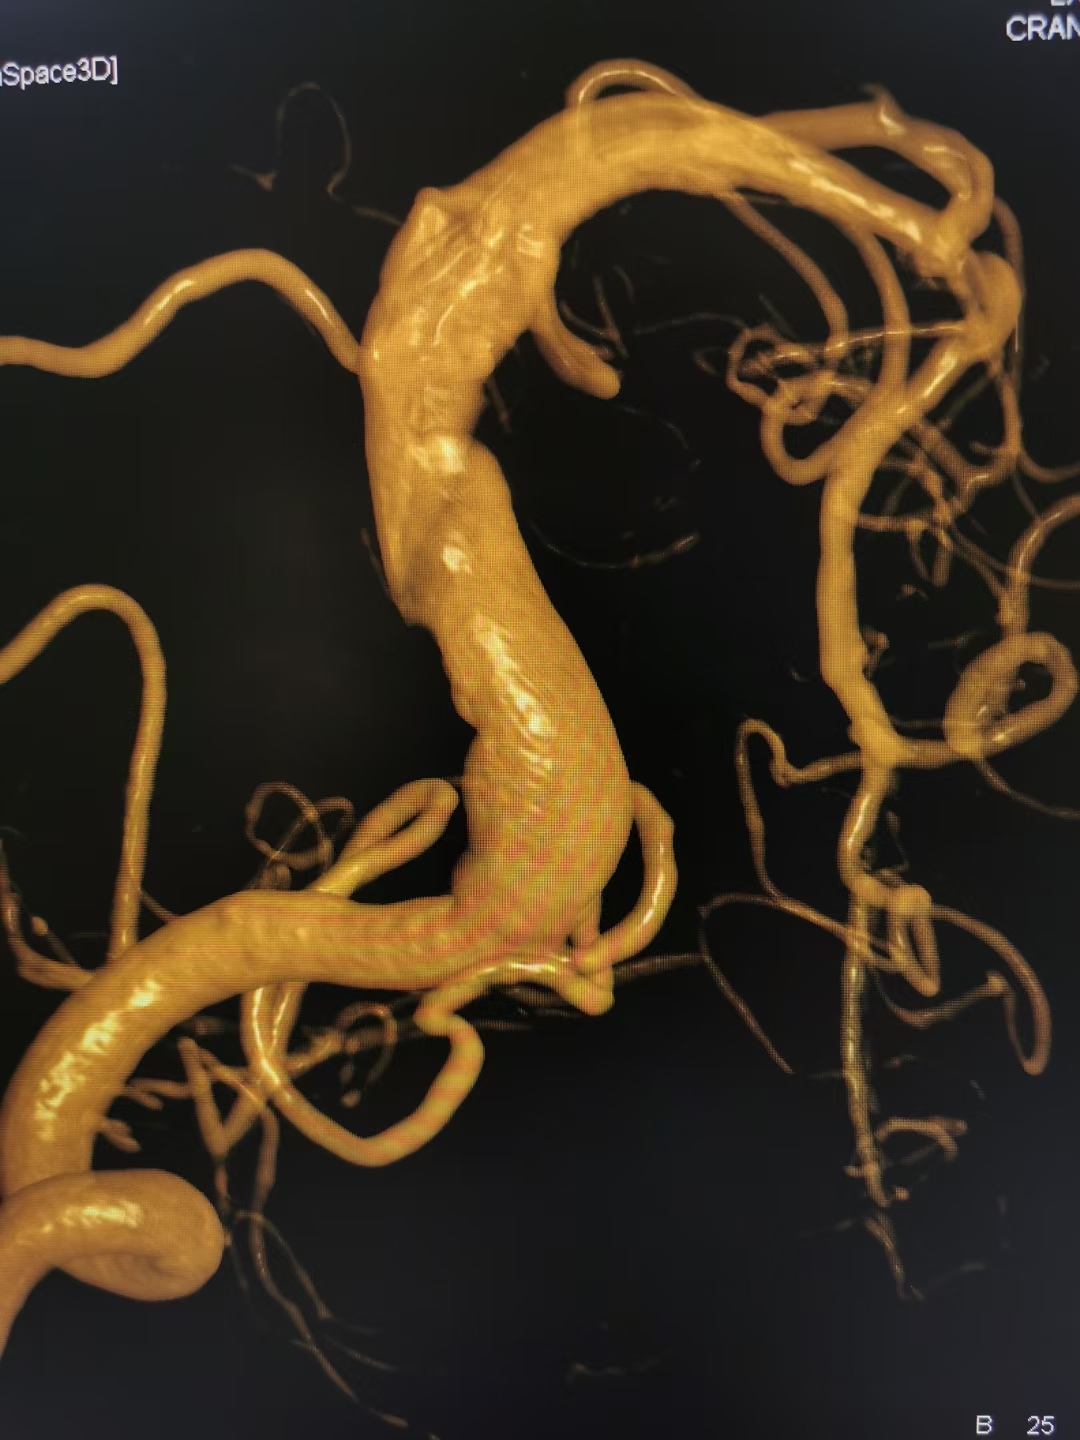

Stroke:椎基底動(dòng)脈擴(kuò)張延長癥的血栓形成過程腦血管病及重癥文獻(xiàn)導(dǎo)讀?2024-01-1506:00?29歲,男性。因急性構(gòu)音障礙和右側(cè)偏癱11小時(shí)就診。CT成像顯示基底動(dòng)脈擴(kuò)張延長。CTA證實(shí)左側(cè)椎動(dòng)脈和基底動(dòng)脈擴(kuò)張延長,基底動(dòng)脈附壁血栓。MRI顯示急性左側(cè)腦橋梗死、基底動(dòng)脈擴(kuò)張和附壁血栓(圖1)。圖1.椎基底動(dòng)脈擴(kuò)張延長癥的附壁血栓。A、冠狀位CTA顯示基底動(dòng)脈擴(kuò)張,伴附壁血栓(白色箭頭)。B、軸位DWI顯示橋腦彌散抑制。C和D,T1MR顯示附壁血栓呈等-高信號(hào)(iso-hyperintensity),提示由新舊血栓混合而成,T2加權(quán)成像顯示等信號(hào)(iso-intense)血栓,管腔高信號(hào),伴有腦干和右海馬受壓(白色箭頭):給予靜脈輸液、替羅非班和強(qiáng)化阿托伐他汀治療。入院12小時(shí)后,患者突然意識(shí)喪失,伴有抽搐和瞳孔不等大。立即CTA顯示急性基底動(dòng)脈閉塞。緊急血栓切除術(shù),并移除一個(gè)大的附壁血栓(圖2)。圖2.患者病情惡化后DSA。A、DSA顯示嚴(yán)重的基底動(dòng)脈擴(kuò)張延長伴急性基底動(dòng)脈閉塞(白色箭頭)。B、取栓后DSA顯示基底動(dòng)脈和雙側(cè)大腦后動(dòng)脈的再通,mTICI評(píng)分為3:20天后,轉(zhuǎn)康復(fù)機(jī)構(gòu),mRS評(píng)分為5,在3個(gè)月的隨訪中預(yù)后不佳。椎基底動(dòng)脈擴(kuò)張延長是一種進(jìn)行性復(fù)雜的腦動(dòng)脈疾病,其特征是椎基底動(dòng)脈異常延長、擴(kuò)張和扭曲,發(fā)病機(jī)制不明。擴(kuò)張延長椎基底動(dòng)脈的血栓可能由新鮮和陳舊成分組成,血栓可以在數(shù)小時(shí)內(nèi)加重,需要更積極的治療。急性血栓形成可以通過靜脈溶栓治療,閉塞性血栓可以采取取栓治療,但療效尚不確定。文獻(xiàn)出處:Stroke.2023Dec;54(12):e494-e495.doi:10.1161/STROKEAHA.123.044834.Epub2023Oct5.AcuteBasilarArteryOcclusionInducedbyRapidlyProgressiveThrombosisinVertebrobasilarDolichoecta